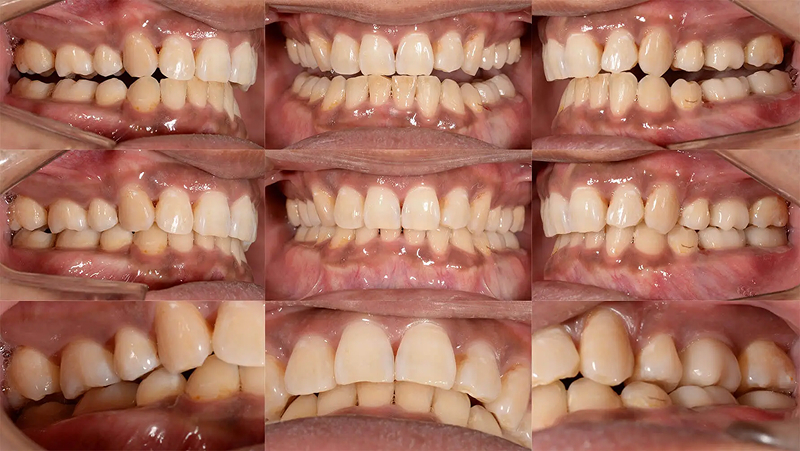

Case03前歯の凸凹を改善した症例

上顎前歯が重なって生えているのを気にされて来院されました。昔から気になっていたが、治療する機会がなく、今回、時間と費用を捻出できそうなので、決断したとのことでした。凸凹は強いですが、口元が元々出ていないタイプだったので、診査の結果、歯列を拡大するだけで非抜歯で可能と診断しました。3年後も安定した状態を保っています。

初診 2015.10.17

矯正治療開始 2015.10.31

ファイナル 2016.5.13

治療3年後 2019.6.8

| 主訴 | 前歯の凸凹が気になる |

|---|---|

| 診断 | 両側アングル1級の叢生 |

| 矯正方法 | オーバーレイアーチを用いたマルチブラケット |

| 矯正期間 | 6か月・7回 |

| 費用 | 690,000円(税別) |

| 調整料 | 月1回 5,000円(税別) |